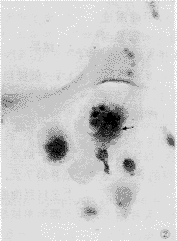

破骨細胞由多核巨細胞(multinuclear giant cell, MNGC)組成,直徑100μm,含有2~50個緊密堆積的核,主要分布在骨質表面、骨內血管通道周圍。由多個單核細胞融合而成的,胞漿嗜鹼性但隨著細胞的老化,漸變為嗜酸性。

在破骨細胞吸收骨基質的有機物和礦質的過程中,造成基質表面不規則,形成近似細胞形狀的陷窩,稱為Howship 陷窩。在陷窩內對著骨質的一面,細胞伸出許多毛樣突起,很象上皮細胞表面的縱紋緣和刷毛緣。電鏡下,貼近骨質的一側有許多不規則的微絨毛,即細胞突起,稱為皺褶緣(ruffled border)。在皺褶緣區的周緣有一環形的胞質區,含多量微絲,但缺乏其它細胞器,稱為亮區(clear zone),此處的細胞膜平整並緊貼在骨質的表面。亮區猶如一道以胞質構成的圍牆,將所包圍的區域形成一個微環境。破骨細胞向局部釋放乳酸及檸檬酸等,在酸性條件下,骨內無機礦物質自皺褶緣吞飲,於皺褶緣基質內形成一些吞飲泡或吞噬泡。於破骨細胞內,無機質被降解,以鈣離子的形式排入血流中。無機質的丟失使骨基質內的膠原纖維裸露,破骨細胞分泌多種溶酶體酶,特別是組織蛋白酶K和膠原溶解組織蛋白酶。破骨細胞離開骨表面後,其皺褶緣消失,細胞內發生變化,進入靜止期。